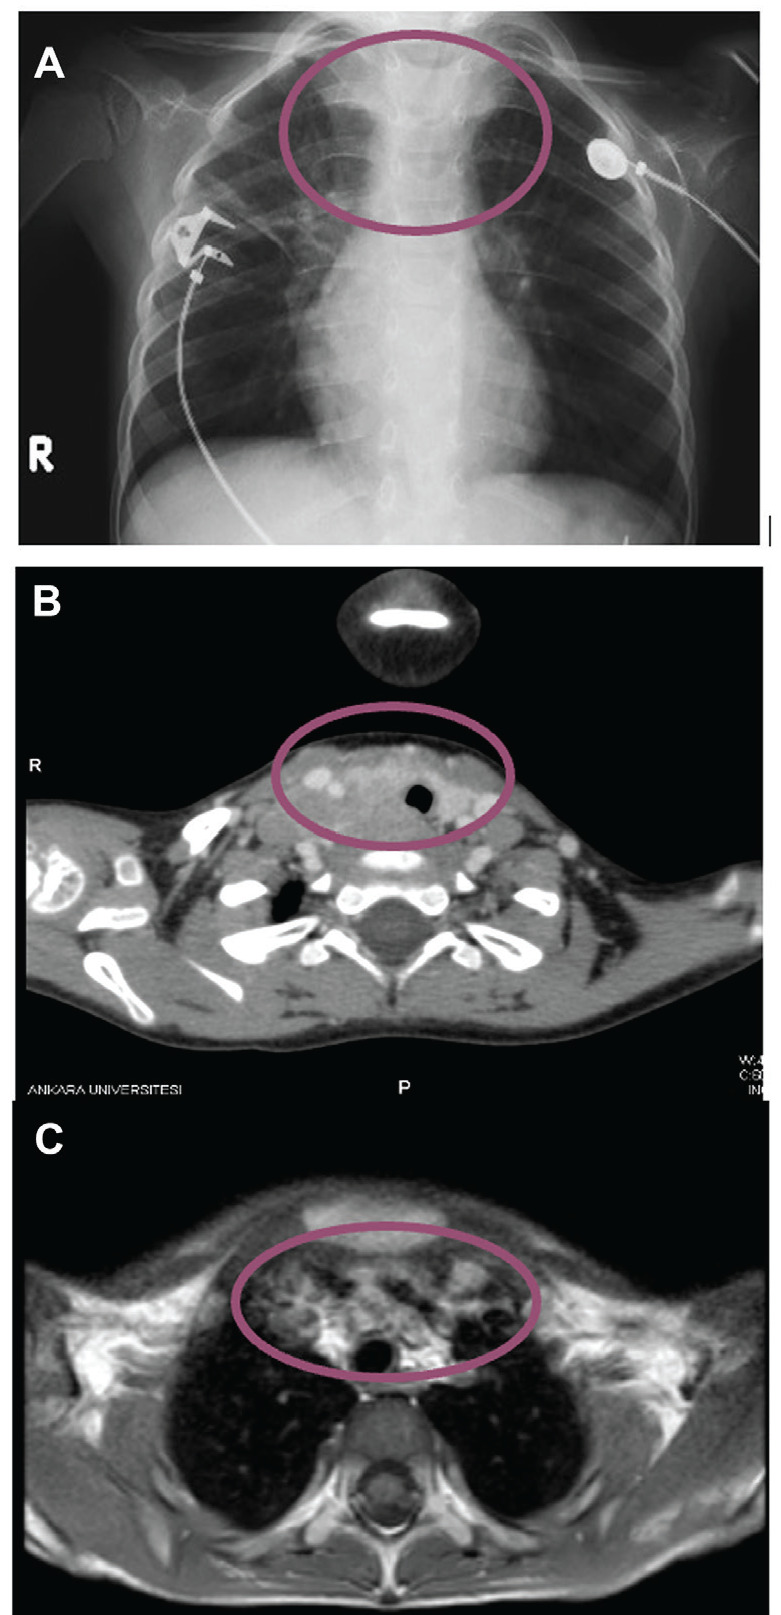

遗传性甲状腺髓质癌(MTC)是罕见的。具有相同突变的不同表型可能是由于RET激活步骤的时间差异、基因其他区域的额外突变或种系和体细胞突变的同时发生,这是一种罕见的可能性。在这里,我们旨在介绍三个具有相同种系突变的家庭成员的不同特征和随访困难。一名患有呼吸窘迫的4岁男性患者被诊断为MTC,并发现RET基因中存在杂合子种系突变C.2671T>G(S891A)(根据ATA分类为中等风险)。由于肿瘤无法手术,开始使用酪氨酸激酶抑制剂(索拉非尼)进行治疗。索拉非尼已经阻止肿瘤进展七年了。全外显子组测序(WES)没有发现额外的突变。分离分析显示,在无症状的母亲和姐妹身上也出现了相同的突变。在我们的病例中,对甲状腺组织进行了体细胞突变检查,发现SDHA c.1223C>T(p.S408L)。携带相同种系突变的家族成员之间,RET p.S891A等罕见突变的临床表现不同。我们的指标病例更严重的临床表现可能是由于额外的体细胞突变。索拉非尼治疗可作为晚期MTC的一种选择,并可预防疾病进展。

Hereditary forms of medullary thyroid carcinoma (MTC) are rare. Different phenotypes with the same mutation may be due to differences in the timing of rearranged during transfection (RET) activation steps, additional mutations in other regions of the gene, or the co-occurrence of germline and somatic mutations, which is an infrequent possibility. Here, we present the different features and challenges during the follow-up of three family members with the same germline mutation. A 4-year-old male patient with respiratory distress was diagnosed with MTC and found to have a heterozygous germline mutation C.2671T>G(S891A) in the RET gene (classified as intermediate risk by the American Thyroid Association. As the tumor was inoperable, treatment with a tyrosine kinase inhibitor (sorafenib) was initiated. This treatment with sorafenib prevented tumor progression for seven years. Whole exome sequencing did not identify additional mutations. Segregation analysis showed the same mutation in the asymptomatic mother and sister. In the proband, thyroid tissues were examined for somatic mutations, and SDHA c.1223C>T (p.S408L) was found. The clinical presentation of rare mutations such as RET p.S891A differed among family members carrying the same germline mutation. Our index case’s more severe clinical presentation may be due to an additional somatic mutation. Sorafenib treatment can be an option for advanced MTC and may prevent disease progression.